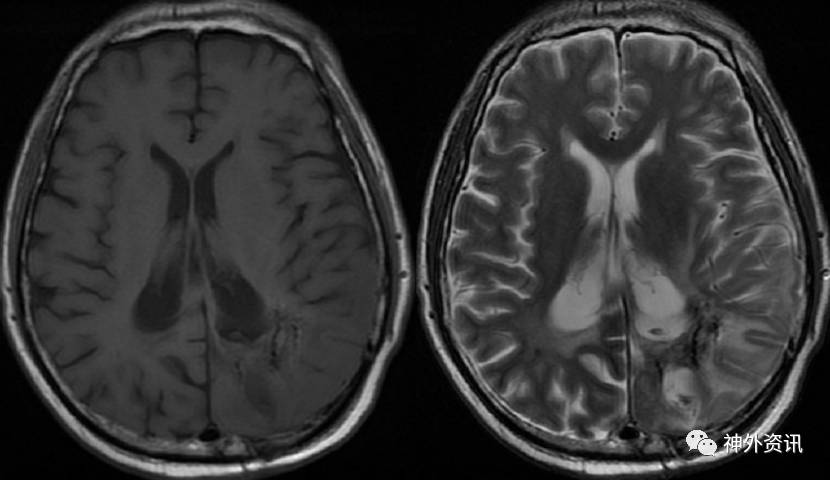

完善术前准备,并经过科室讨论后,于2016.8.16行立体定向125I粒子植入术,术前复查头颅MRI增强,提示激素使用后,肿瘤未见明显缩小。根据放射性粒子植入计划系统(TPS)系统,设计7个穿刺道,共计植入34颗125I粒子(图5)。

图5. MRI检查肿瘤未见明显缩小。TPS系统设计7个穿刺道。

手术顺利,术后予以脱水、激素(甲强龙40mg Qd)及对症支持治疗,患者病情平稳。复查头颅MRI增强(2016.8.22):左侧脑室后角旁不规则形异常信号,呈T1、T2等信号,内见小片T2稍高信号,增强后呈明显强化,强化欠均匀,周边见大片T1低信号、T2高信号水肿区。对比前片(2016-07-12)肿块明显缩小(图6)。

图6. MRI检查:左侧脑室后角旁不规则形异常信号,呈T1、T2等信号,内见小片T2稍高信号,增强后呈明显强化。